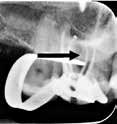

Fig. 8. Skematisk illustration af (A) en præmolar med 30º lingval kipning (18). Bor viser potentielt område for perforation (B) præmolar med 30º rotation (C) underkæbeincisiv med let/moderat kipning af roden, men overkontureret krone. Bor viser potentielt område for perforation. D. præmolar med distal kipning og molar med mesial kipning. Bor viser potentielt område for perforationer (18). E. Røntgenoptagelse af molar med let til moderat mesial kipning; bor viser perforationsområde.

F. Røntgenoptagelse af tand med mesialt placeret oplukningskavitet og fremmedlegeme i alveoleknoglen som følge af perforation.

Fig. 8. Schematic illustration of (A) a premolar with 30º lingual tilt (18). Bur showing potential area of perforation (B) premolar with a 30º rotation (C) lower incisor with a mild/moderate tilt in the root but an over-contoured crown. Bur showing potential area of perforation. D. premolar with distal tilt and molar with mesial tilt. Bur showing potential area of perforations (18). E. Radiograph showing a molar with a mild to moderate mesial tilt with bur showing area of perforation. F. Radiograph of tooth with mesially placed access cavity preparation and foreign material lodged in the alveolar bone due to perforation.

En tandlæge i Kategori A har ikke erhvervet tilstrækkelige færdigheder til at kunne modificere oplukningskavitetens udformning i en tand, der er kippet eller roteret. For at undgå unødvendige uheld som perforation i forbindelse med oplukningen (Fig. 8A-F) bør sådanne tænder kun behandles af tandlæger, der mindst er i Kategori B.